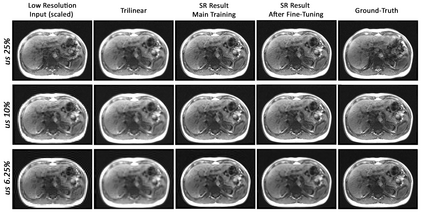

Dynamic imaging is a beneficial tool for interventions to assess physiological changes. Nonetheless during dynamic MRI, while achieving a high temporal resolution, the spatial resolution is compromised. To overcome this spatio-temporal trade-off, this research presents a super-resolution (SR) MRI reconstruction with prior knowledge based fine-tuning to maximise spatial information while preserving high temporal resolution of dynamic MRI. An U-Net based network with perceptual loss is trained on a benchmark dataset and fine-tuned using one subject-specific static high resolution MRI as prior knowledge to obtain high resolution dynamic images during the inference stage. 3D dynamic data for three subjects were acquired with different parameters to test the generalisation capabilities of the network. The method was tested for different levels of in-plane undersampling for dynamic MRI. The reconstructed dynamic SR results after fine-tuning showed higher similarity with the high resolution ground-truth, while quantitatively achieving statistically significant improvement. The average SSIM of the lowest resolution experimented during this research (6.25~\% of the k-space) before and after fine-tuning were 0.939 $\pm$ 0.008 and 0.957 $\pm$ 0.006 respectively. This could theoretically result in an acceleration factor of 16, which can potentially be acquired in less than half a second. The proposed approach shows that the super-resolution MRI reconstruction with prior-information can alleviate the spatio-temporal trade-off in dynamic MRI, even for high acceleration factors.